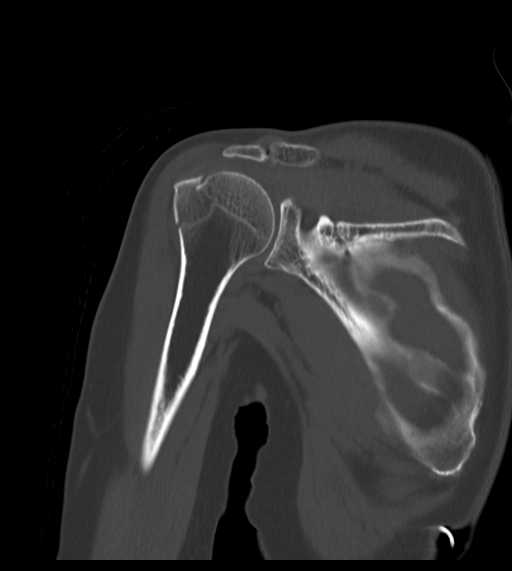

整形外科領域

四肢

骨折(肩)